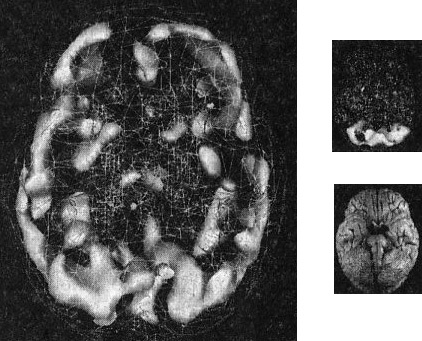

Наконец, рис. Г показывает трехмерную картину активности здорового мозга, вид снизу, а под ней находится иконка с моделью мозга в той же проекции. ![]() Помните, что трехмерные поверхностные сканы помогают увидеть малоактивные области, а трехмерные функциональные сканы помогают обнаружить гиперактивные области. Как не бывает двух одинаковых лиц, так нельзя встретить и два одинаково выглядящих мозга. С эстетической точки зрения бывают красивые и уродливые, банальные и причудливые мозги. Но всегда справедливо — и это доказали 30 000 проведенных мною сканирований, — что активность здорового мозга должна быть достаточной, полной, равномерной и симметричной. В здоровом мозге целы все важные участки, и все они работают гармонично. Возрастные вариации нормальны. Сканы мозга детей и подростков показывают большую активность, чем у взрослых. Но даже у пожилых людей мозг будет здоровым, если о нем заботились в течение жизни. Давайте взглянем на несколько примеров здорового и не очень здорового мозга. Однажды я предложил студентам стать добровольцами в исследовании функционирования мозга. Кристи, одна из вызвавшихся, воскликнула: «Вам обязательно нужно проверить мою бабушку Анну. Ей 82 года, но среди всех, кого я знаю, она одна из самых нормальных. Она вам понравится!» Бабушка согласилась, и мы провели томографию. Действительно, обнаружилось, что мозг этой пожилой женщины здоров, а ее жизнь соответствует всем критериям профилактики здоровья мозга (она не употребляла наркотики, не получала травм головы, не имела родственников первой степени с психиатрическими заболеваниями и т. д.). В течение 58 лет Анна была замужем, всегда оставаясь любящей женой, матерью и бабушкой, ее ум был острым и деятельным. Кроме того, она активно участвовала в делах местной церкви и муниципалитета. Она создала прочные и длительные отношения с родными и друзьями. Скан мозга Анны — один из самых здоровых в моей базе данных (рис. 2.5 и 2.6). Скан здорового мозга Анны, 82 года Рис. 2.5 Вид сверху Полная симметричная активность ![]() Рис. 2.6 Вид снизу Полная симметричная активность ![]() Двадцатилетний Брюс, несмотря на молодость, годами злоупотреблял наркотиками: героином, марихуаной, амфетаминами, галлюциногенами, экстази и обезболивающими. Я познакомился с ним, когда снимал образовательный фильм о вреде наркотиков. Брюс не был способен завязать со своим пристрастием. Отношения с родными разладились. Он стыдился себя и своего поведения. Как вы сами можете увидеть, мозг 82-летней Анны на томограмме выглядит значительно здоровее поврежденного наркотиками мозга молодого Брюса (рис. 2.7). Поврежденный наркотиками мозг Брюса Рис. 2.7 Вид сверху Значительные повреждения ![]() В норме с возрастом мозг становится все менее активным, поэтому если очень пожилая женщина обладает значительно более здоровым мозгом, чем 20-летний парень, значит, у этого парня серьезные неприятности. Я убедился, что люди со здоровым мозгом ведут себя эффективно и всегда движутся к поставленным целям. Они прекрасные сотрудники, супруги, родители, друзья и граждане. Люди же с поврежденным мозгом с трудом бредут по жизни. Вспомните про болезнь Альцгеймера (БА): можно ли сказать, что заболевшие ею способны полноценно проявлять свою волю и личность? Вероятно, нет. У людей с БА функционал мозга значительно поврежден. От этой болезни страдала мать моей подруги Айзы Гиббонс, основавшей ряд центров поддержки для людей с БА и членов их семей. Мать Лизы из доброй, мягкой женщины превратилась в озлобленного, иррационального и агрессивного человека (рис. 2.8). Мозг пациента с болезнью Альцгеймера Рис. 2.8 Вид сверху Значительно снижена активность в задних частях мозга ![]() Гиперактивность мозга часто связана с обсессивно-компульсивным [2] и биполярным расстройствами и другими заболеваниями. 17-летняя Хитер очень много пила и не ладила с семьей. Я сделал томографию мозга ей и ее брату для телепередачи «Правда о выпивке», которая позже получила премию «Эмми». На сканах вы видите области очень высокой активности (рис. 2.9). Неудивительно, что девушка начала пить — она пыталась успокоить свой мозг. Гиперактивный мозг Хитер Рис. 2.9 Вид функциональной активности снизу Значительно снижена общая активность ![]() 45-летний Джимми обратился ко мне с посттравматическим стрессовым расстройством, вызванным пожаром. Томограмма показала множественные области повышенной активности, о которых можно было догадаться, судя по его тревожности, депрессии и страхам. Эмоциональные центры его мозга работали чересчур напряженно, и моей задачей было их успокоить (рис. 2.10). Гиперактивный мозг Джимми Рис. 2.10 Вид функциональной активности снизу Повышенная активность в глубоких областях мозга ![]() А теперь вернемся к разнице между «волевым» и «мозговым поведением». Плохо работающий мозг лишает людей силы воли и провоцирует деструктивные поступки. Люди с обсессивно-компульсивным расстройством (ОКР), синдромом Туретта (СТ) или зависимостью от наркотиков, скорее всего, стали жертвами своего мозга. Для ОКР характерны вызывающие огорчение навязчивые мысли или компульсивное поведение (непрерывная проверка дверных замков, постоянное мытье рук, следование ритуалам). Даже если человек понимает, что его мысли и поступки иррациональны, он все равно не может от них отказаться. В тяжелых случаях такие мысли и действия занимают большую часть дня. Сканы показывают, что при ОКР гиперактивна передняя часть мозга, провоцирующая навязчивые мысли (обсессия) или действия (компульсия). |